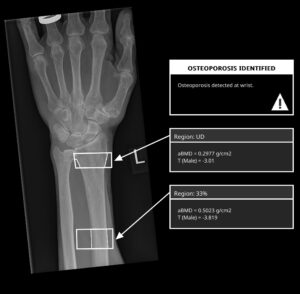

3 . बोन डेंसिटी टेस्ट (DEXA Scan)

ऑस्टियोपोरोसिस की पहचान के लिए DEXA Scan (Dual-Energy X-ray Absorptiometry) किया जाता है। यह हड्डियों की घनत्व मापता है।

T-Score का मतलब:

-1 से ऊपर = सामान्य

-1 से -2.5 = Osteopenia

-2.5 से कम = Osteoporosis